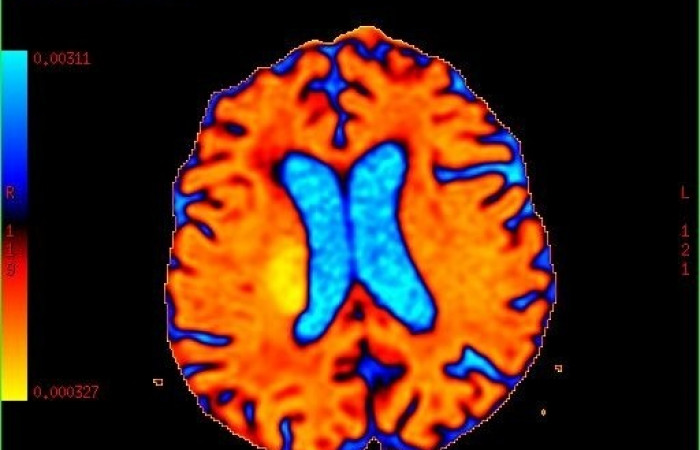

- obrazowanie perfuzji mózgu,

ˇ badanie perfuzyjne mózgu (z i bez środka kontrastowego)

ˇ czynnościowe obrazowanie mózgu (fMRI)

- Spektroskopia MR, która pozwala na przedstawienie patologii na poziomie metabolizmu, kiedy brak jest jeszcze zmian w obrazach morfologicznych. System umożliwia wykonywanie badań w opcji spektroskopii protonowej (HMRS) a także fosforowej (PMRS).

- Funkcjonalne obrazowanie MR (fMRI) mózgu, które umożliwia identyfikację ośrodków neuronalnych, odpowiedzialnych za czynności takie jak poruszanie kończynami, mowa, widzenie czy funkcje wyższe. Pozwala także na tzw. mapowanie przed zabiegami neurochirurgicznymi - ocenia się wzajemny stosunek guza do ośrodków neuronalnych odpowiadających za określone czynności w celu minimalizacji następstw zabiegu.